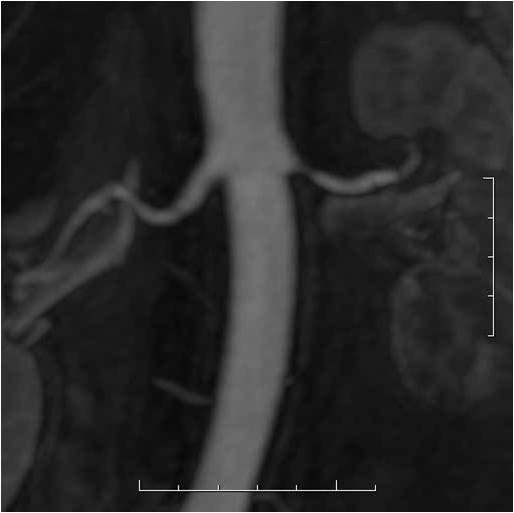

CTA and MRA are both capable of diagnosing renal artery stenosis. Both methods can identify anatomic variations, atherosclerotic lesions at the origin of the vessels or at distal segments on the artery. These techniques not only show the contour irregularities and the narrowed lumen, but they are also able to reveal the secondary parenchymal lesion of the kidney. However, in patients with decreased renal function, both types of contrast materials should be avoided or applied only with care.

Image

Contrast enhanced MR angiography

Control CT angiography after stent implantation to correct a bilateral arterial stenosis

Fig. 18., 19.: Renal artery stenosis